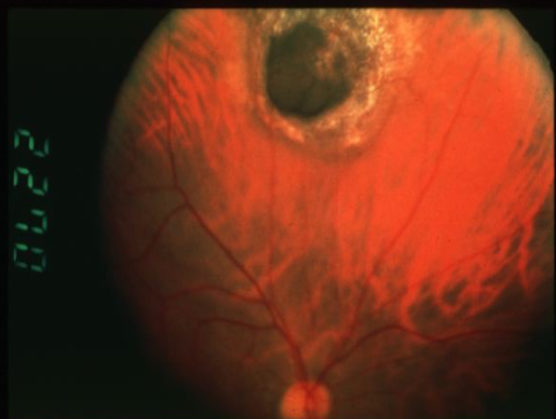

endophytic

retinoblastoma type

white, pearly-pink, creamy nodular mass that breaks through the ILM into vitreous

vitreous seeding

fine blood vessels on surface

secondary calcification leads to sharp demarcations (cottage cheese)

multiple tumors possible

retinoblastoma

retinoblastoma

retinoblastoma